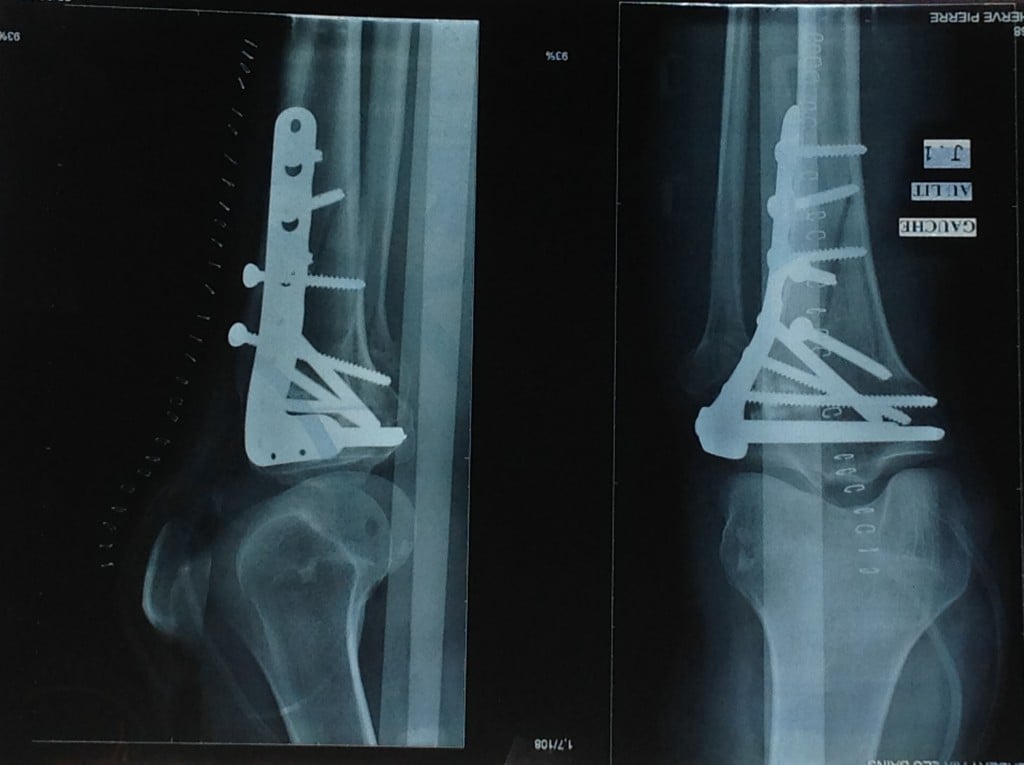

This narrative recounts my fourth knee surgery, the third at HSS. A decade ago, I sought care at HSS following a tibial plateau fracture operated on in the Alps. Dr. Helfet oversaw my recovery and later performed hardware removal on my severely osteoporotic bone. Unfortunately, eight years later, I broke the same knee again in the Alps. Without hesitation, I flew back to New York, confident beyond any doubt that HSS would provide unparalleled orthopedic care.

In an incredible three-hour surgery, Dr. Helfet reconstructed my shattered knee cap into no fewer than 20 pieces. Eleven months later, after a flawless recovery, Dr. Helfet and I decided to remove the 10 screws and plate. Once again, he successfully navigated surgery on my genetically fragile bone.